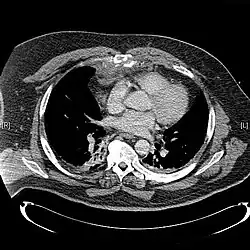

Сверху: грудина окрашена цветом морской волны. Внизу: компьютерная томограмма оскольчатого перелома грудины.[1] | |

Выполняют рентгенографию грудной клетки в боковой проекции для подтверждения диагноза.